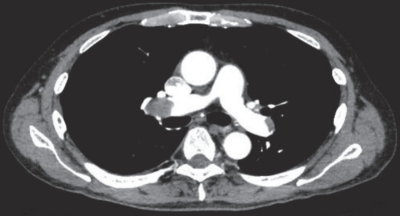

体温36.4℃。脈拍84/分、整。血圧114/70mmHg。呼吸数18/分。SpO2 92%(room air)。鼻カニューラ2L/分で酸素投与したところ、SpO2は99%となった。心音と呼吸音に異常を認めない。腹部は平坦で、肝・脾を触知しない。術創部からの出血は認めない。胸部造影CTを別に示す。